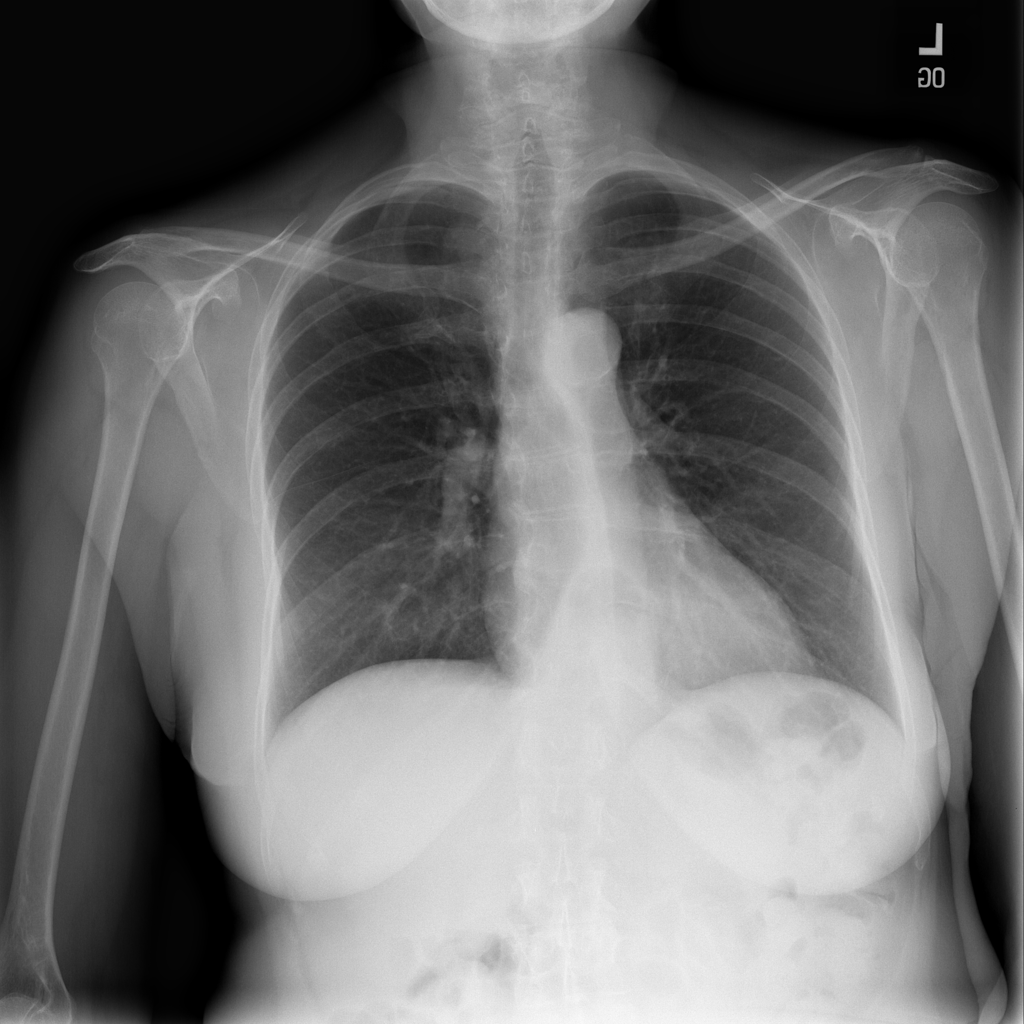

PAT-C048 · IMG-000Hernia

PAT-C048 · IMG-000

PA